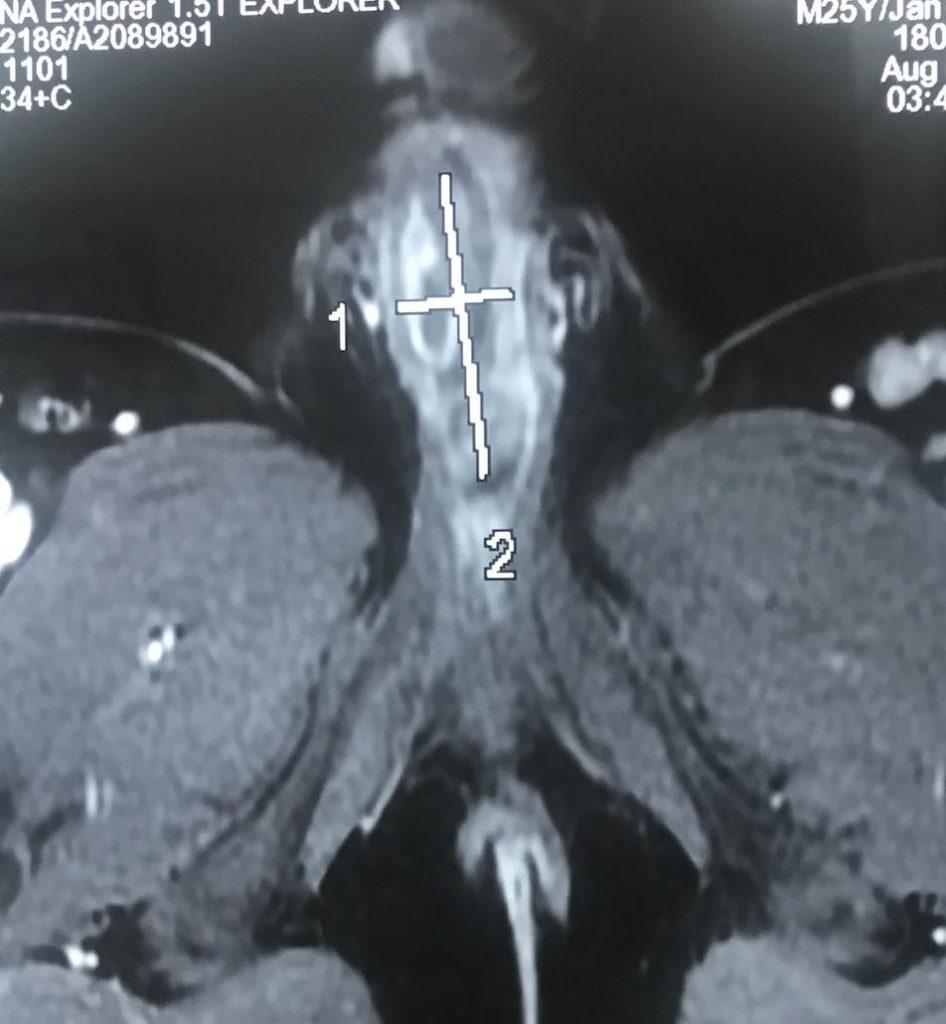

Được chuyển đến Bệnh viện Bình Dân với chẩn đoán viêm loét dương vật trên bệnh nhân có lỗ tiểu thấp thể dương vật. Anh T.H.N. cho biết hơn 10 năm nay, anh thường đi tiểu đau, cảm giác gắt buốt và nước tiểu đục, có lúc tiểu mủ. Vài tháng gần đây, tình trạng đau ngày càng trở nên tồi tệ hơn, người bệnh tiểu khó, da thân dương lở loét và đau đớn. Các kết quả chẩn đoán hình ảnh (như X-quang bàng quang – niệu đạo, siêu âm Doppler tinh hoàn – mào tinh, cho thấy hình ảnh một vật lạ chưa rõ bản chất đang nằm trong niệu đạo.

Hình ảnh dị vật qua siêu âm doppler

Trong quá trình phẫu thuật thám sát đường tiểu, ê kíp phẫu thuật phát hiện một vật lạ đã ăn sâu xuyên qua thành niệu đạo đến sát vách thể hang của dương vật. Dị vật được lấy khỏi niệu đạo là một đoạn dây cước câu cá đã đóng sỏi xung quanh thành khối có kích thước 2,5cmx6cm.